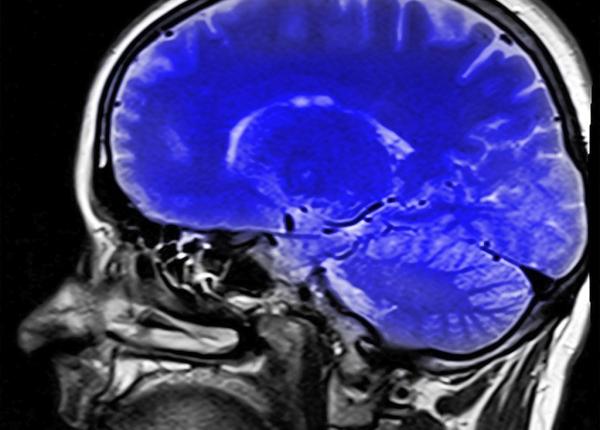

Cercetători germani au analizat relația dintre demența la vârstnici și medicamentele antihipertensive. Studiul a inclus circa 25.000 de persoane.